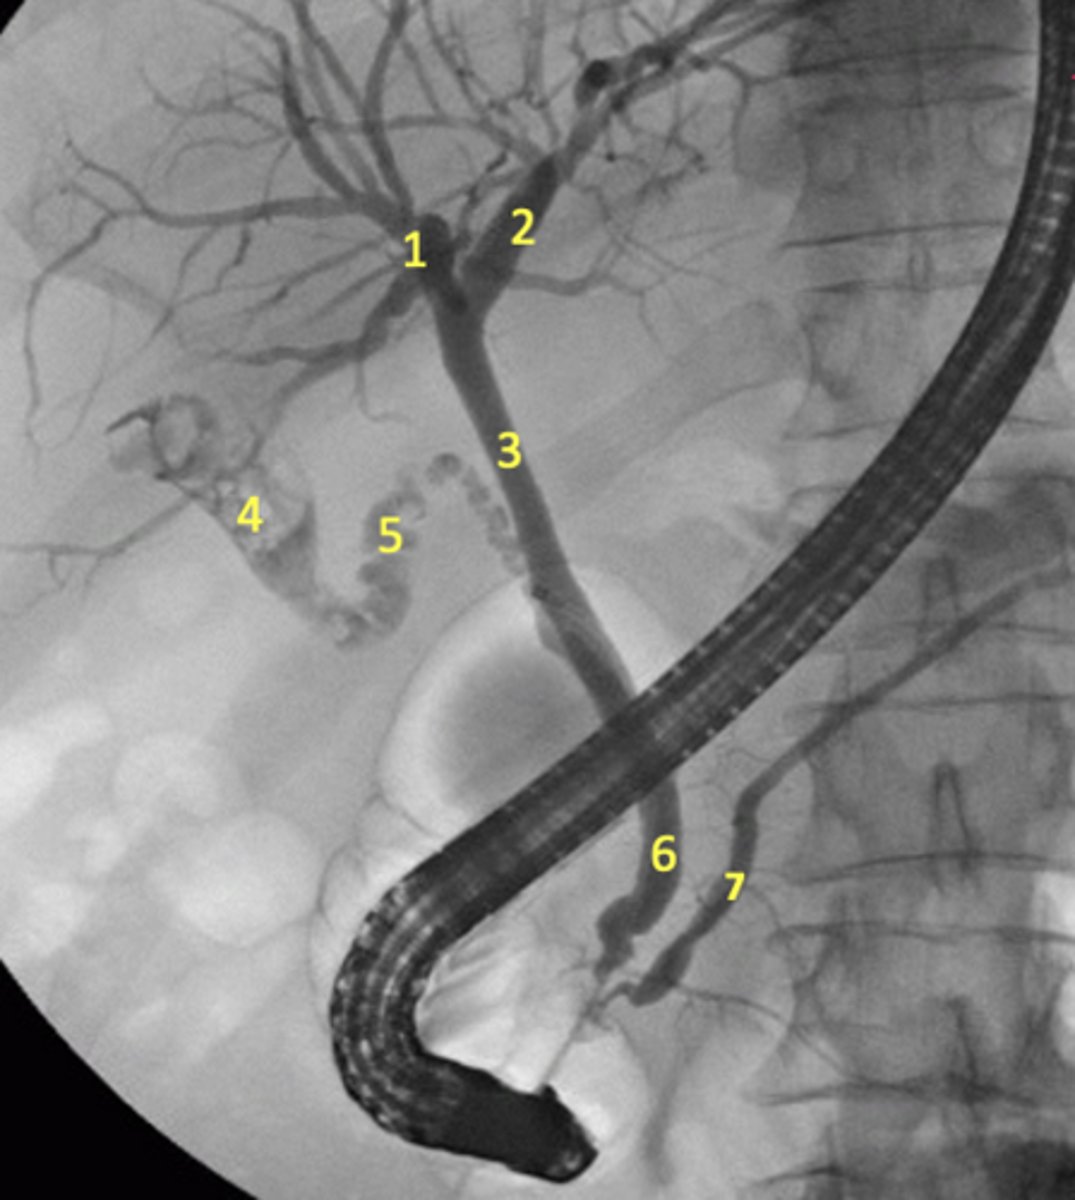

1. R hepatic duct

2. L hepatic duct

3. Common hepatic duct

4. Gallbladder

5. Cystic duct

6. Common bile duct

7. Pancreatic duct (major)

Endoscope also seen

Label the radiograph